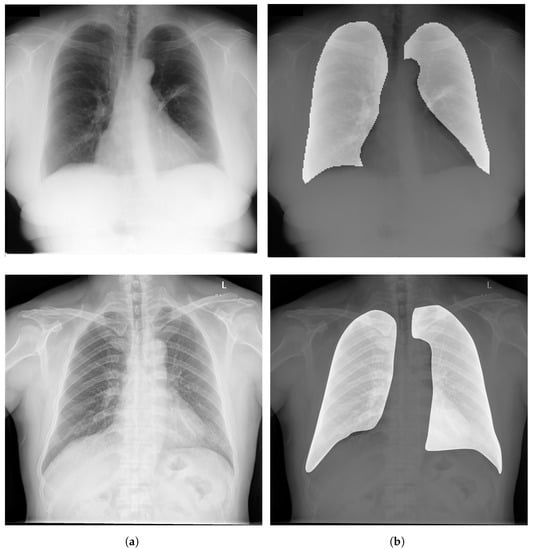

Image Segmentation has a critical rule in image preprocessing techniques. It is usually necessary to divide a visual image into fragments. For CXR images, this technique allows segmenting the thoracic image into areas in order to extract the ROI. Figure 6 depicts examples of ROIs overlaid on CXR images.

Figure 6.

(a) Examples of CXR images from CheXpert dataset [44]; (b) Samples of ROIs overlaid on CXR images.